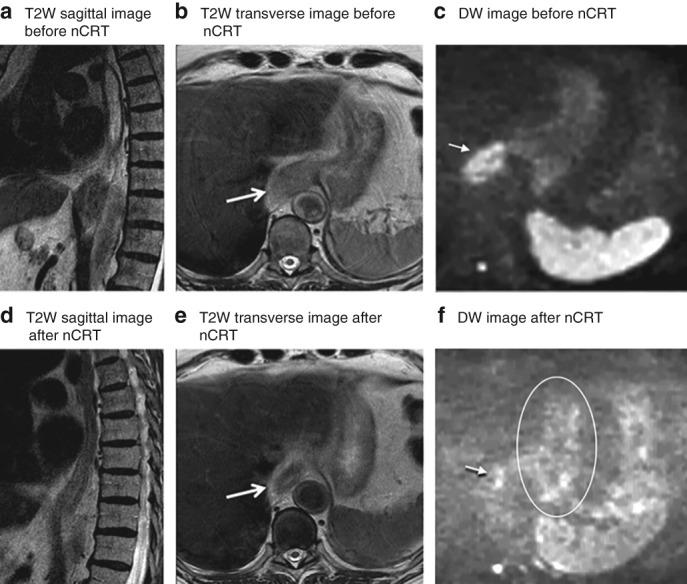

Patients with a pathological complete response (pCR) after neoadjuvant chemoradiotherapy (nCRT) for oesophageal cancer may benefit from non-surgical management. The aim of this study was to determine the diagnostic performance of visual response assessment of the primary tumour after nCRT on T2-weighted (T2W) and diffusion-weighted (DW) MRI.

Patients with locally advanced oesophageal cancer who underwent T2W- and DW-MRI (1·5 T) before and after nCRT in two hospitals, between July 2013 and September 2017, were included in this prospective study. Three radiologists evaluated T2W images retrospectively using a five-point score for the assessment of residual tumour in a blinded manner and immediately rescored after adding DW-MRI. Histopathology of the resection specimen was used as the reference standard; ypT0 represented a pCR. Sensitivity, specificity, area under the receiver operating characteristic (ROC) curve (AUC) and interobserver agreement were calculated.

Twelve of 51 patients (24 per cent) had a pCR. The sensitivity and specificity of T2W-MRI for detection of residual tumour ranged from 90 to 100 and 8 to 25 per cent respectively. Respective values for T2W + DW-MRI were 90-97 and 42-50 per cent. AUCs for the three readers were 0·65, 0·66 and 0·68 on T2W-MRI, and 0·71, 0·70 and 0·70 on T2W + DW-MRI (P = 0·441, P = 0·611 and P = 0·828 for readers 1, 2 and 3 respectively). The κ value for interobserver agreement improved from 0·24-0·55 on T2W-MRI to 0·55-0·71 with DW-MRI.

Preoperative assessment of residual tumour on MRI after nCRT for oesophageal cancer is feasible with high sensitivity, reflecting a low chance of missing residual tumour. However, the specificity was low; this results in overstaging of complete responders as having residual tumour and, consequently, overtreatment.